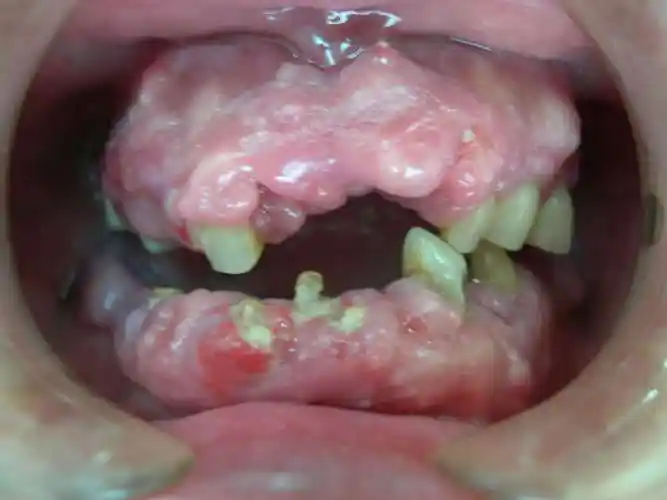

病历3 慢性牙周炎术后口内照